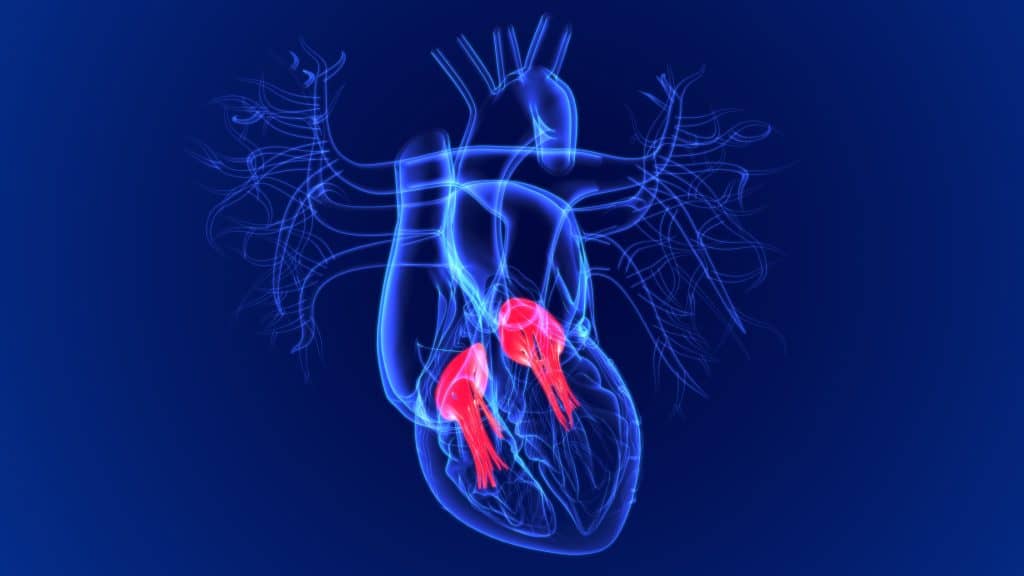

Srčani zalistak je ventil koji propušta krv do komore srca. U srcu čovjeka su prisutna četiri zaliska te oni skupa određuju put protoka krvi kroz srce. Zalistak se otvara kada propušta krv, te se zatvara kako se ispuštena krv ne bi ponovno vratila natrag u srce. Srčani zalisci su obloženi endokardom, te se svaki zalistak nalazi u jednoj klijetki. Srčani zalisci se nalaze oko fibroznih prstenova srčanog skeleta. Svaki zalistak sadrži male zaliske koje se nazivaju kvržicama ili listićima koje se otvaraju kako bi krv mogla proći, te se potom zatvaraju kako bi se spriječio povratak ispuštene krvi.

Svaka klijetka ima valvulu kroz koji krv te valvulu kroz koju izlazi krv. Ponekad se dogodi da ventilni otvori se ne otvaraju i zatvaraju kako trebaju, te to posljedično može narušiti protok krvi kroz srce i tijelo. Srčani zalisci su složene strukture, te njihova je funkcija da služe kao ventil. Srčani zalisci su smješteni između klijetke i pretklijetke, odnosno između arterije i klijetke koja izlazi iz srca prema van.

Postoje četiri vrste srčanih zalistaka:

- mitralni zalistak čija je uloga da spriječi ponovno vraćanje krvi iz lijeve klijetke u njegovu lijevu pretklijetku

- aortni zalistak čija je uloga koji nakon istiskivanja krvi iz klijetke da zadrži krv u aorti

- trikuspidalni zalistak čija je uloga da spriječi vraćanje krvi iz desne klijetke u njegovu desnu pretklijetku

- pulmonalni odnosno plućni zalistak čija je uloga nakon istiskivanja iz desne klijetke da zadrži krv u pulmonalnoj arteriji